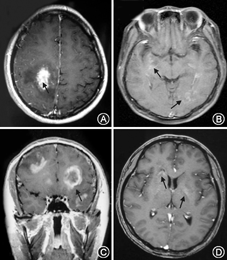

单纯脑干受累的TDL 2例,大脑半球受累56例。病变单侧受累24例(41.3%),双侧受累34例(58.7%);单发病灶22例(37.9%),多发病灶36例(62.1%)。TDL急性期以斑片样或结节样强化为主(图1A),[在超急性期或急性早期(≤7~10 d)增强扫描仅见线状或小片状强化(图1B)];亚急性期以周边强化明显为特点,呈现出环形或"C"形强化(图1C),但有时因其处于炎症反应的不同阶段或病灶大小的不同,其影像学表现不尽相同,也可呈现出急性期的斑片样或结节样强化;慢性期病灶呈轻度线性、小片状环形浅淡强化(图1D),部分病灶强化消退。